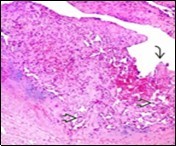

On microscopy, superficial squamous epithelial surface is intact. Sub-epithelial connective tissue stroma exhibits slit-like, vascular spaces. Upon extended magnification, multiple, intravascular papillary projections encompassed within a hyalinised stroma are discerned. Centroidal calcification appears in combination with intravascular, papillary endothelial cell proliferation, lined with singular layer of endothelial cells devoid of cytological atypia6, 7.

Characteristically, the vascular neoplasm denominates numerous papillae within blood vessels. Papillae are coated with singular or dual layer of flattened endothelial cells with an encompassing hyalinised, fibrous tissue core. Vascular lumen is distended with thrombosis. Foci of haemorrhage with fibrinous and purulent exudate are discerned. Tumour perimeter depicts inflammatory granulation tissue. Cholesterol clefts and focal reactive bone formation may concur. Extraneous squamous epithelium may be discontinuous and ulcerated. The neoplasm is devoid of features of malignancy4, 6.

Numerous micro-calcifications can be observed within the lesion which may engender vascular occlusion and tissue necrosis6. Figure 1, Figure 2, Figure 3, Figure 4, Figure 5, Figure 6, Figure 7, Figure 8.

Figure 2 Papillary endothelial hyperplasia delineating papillary articulations with an endothelial cell layer, thrombotic exudate and fibrinous debri (1.